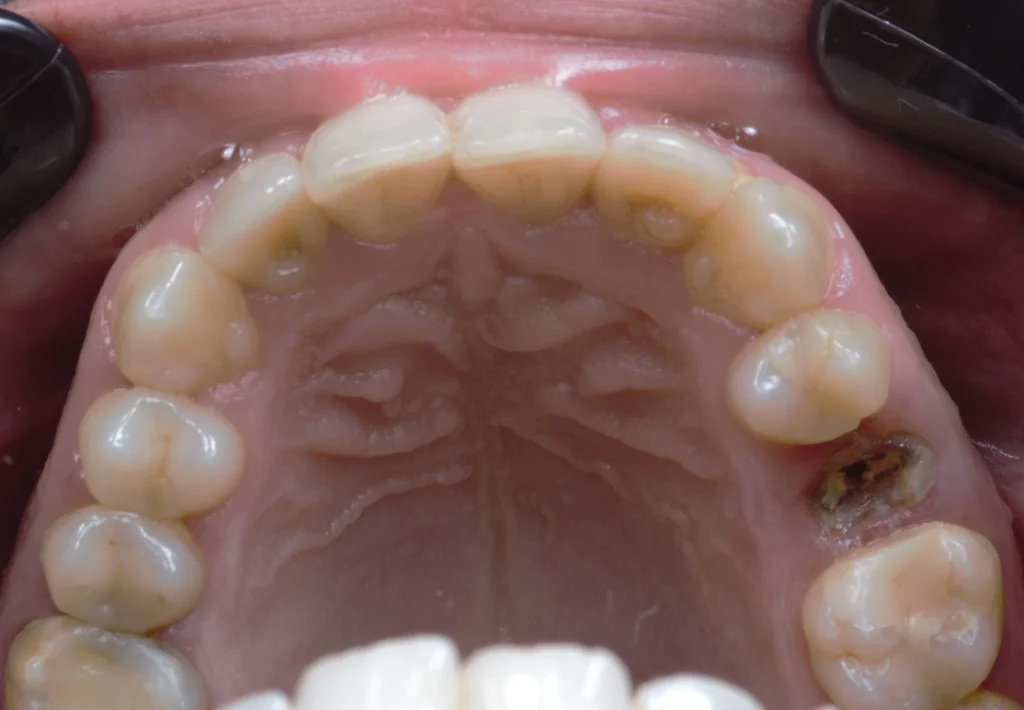

This patient came to our office with a broken upper second premolar that could no longer be saved. The damage was extensive, and the tooth had no long-term prognosis, making extraction the only viable option.

After a thorough clinical evaluation, we determined that a dental implant would be the best solution to restore both function and aesthetics. The goal was to achieve a natural-looking result while preserving the surrounding bone and tissues.